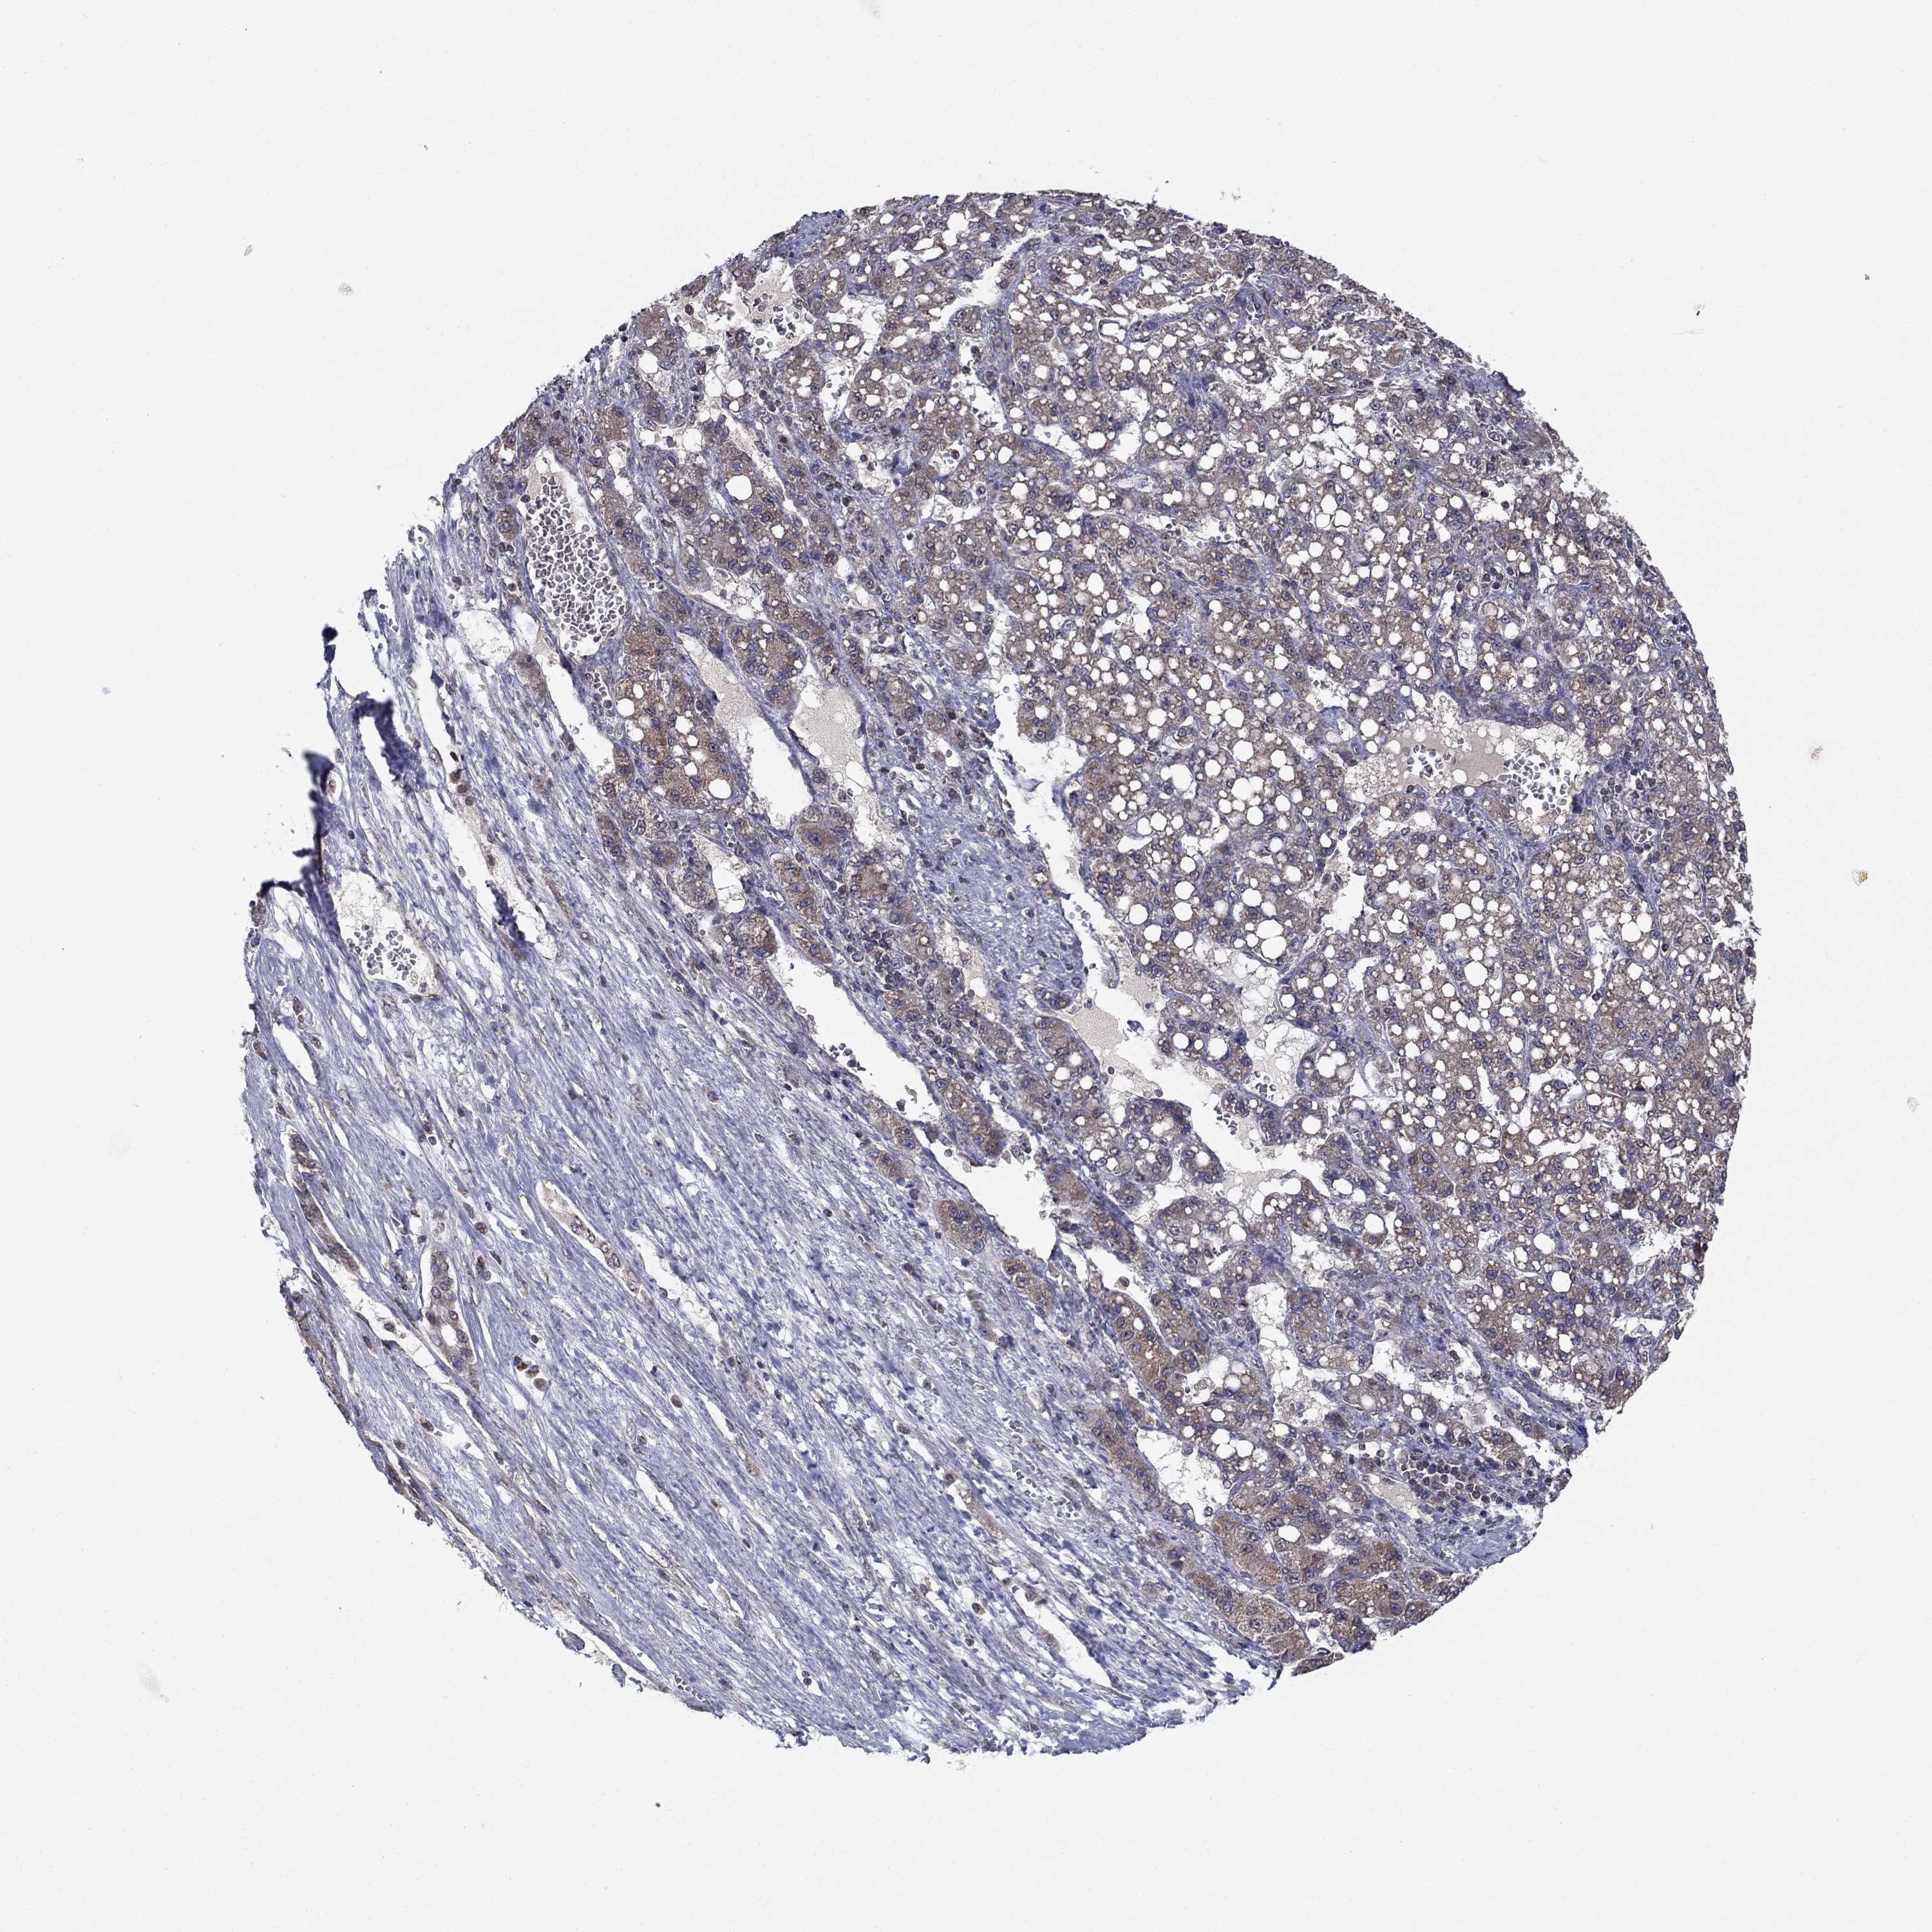

LIVER CANCER - Protein expressioni

A mouse-over function shows sample information and annotation data. Click on an image to view it in a full screen mode. Samples can be filtered based on level of antibody staining by selecting one or several of the following categories: high, medium, low and not detected. The assay and annotation is described here.

Note that samples used for immunohistochemistry by the Human Protein Atlas do not correspond to samples in the TCGA dataset.

Antibody stainingi

Antibody staining in the annotated cell types in the current human tissue is reported as not detected, low, medium, or high, based on conventional immunohistochemistry profiling in selected tissues. This score is based on the combination of the staining intensity and fraction of stained cells.

Each image is clickable and will lead to virtual microscopy that enables deeper exploration of all samples and also displays staining intensity scores, fraction scores and subcellular localization as well as patient and tissue information for each sample.

Antibody HPA006584

Antibody HPA061679

Staining

High

Medium

Low

Not detected

Intensity

Strong

Moderate

Weak

Negative

Quantity

>75%

75%-25%

<25%

None

Location

Nuclear

Cytoplasmic/membranous

Cytoplasmic/membranous,nuclear

Cholangiocarcinoma

Carcinoma, Hepatocellular, NOS